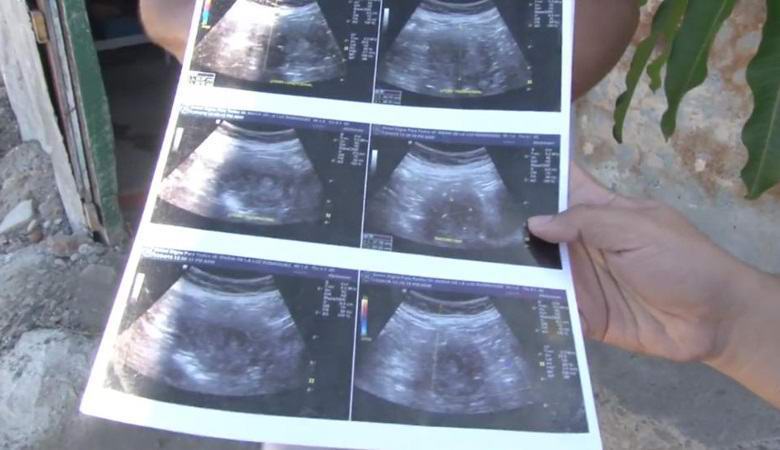

Tuleva työnantajanainen nainen näytti ultraäänivalokuvia toimittajille, maailmanrekisterin asettamiseksi hänen pitäisi kuitenkin virallisesti dokumentoi raskautesi. Tuomari ultraäänellä kuvia, meksikolainen odottaa tytön syntymää.